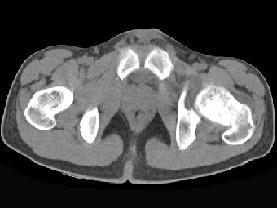

问题 患者,女,19岁,左髋疼痛、活动受限伴跛行6个月,无发热、盗汗病史,曾考虑左髋关节结核并抗结核治疗2周,症状有一定缓解,请结合所提供图像,选择最佳答案 ( )

选项 A、骨化性纤维瘤 B、骨囊肿 C、非骨化性纤维瘤 D、软骨母细胞瘤 E、骨样骨瘤

答案 D